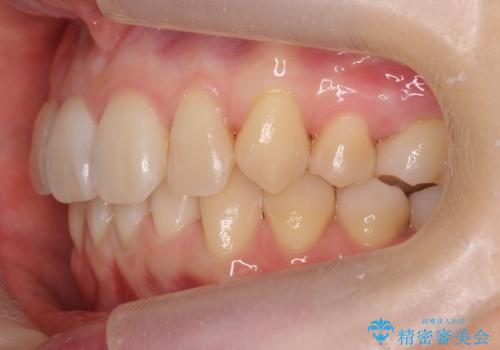

左上の犬歯が入りきらずねじれており、かみ合わせもずれていました。

前歯は内側に傾いており(ラビッティング)、過蓋咬合(深いかみ合わせ)を呈していました。

難しい治療でしたが綺麗に咬み合わせることができ、また前歯もしっかり当たるように治療できました。